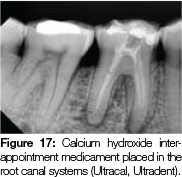

A 56-year old female patient was referred for endodontic treatment of her lower right first molar after she presented with an acute absess. Radiographic examination revealed a fractured restoration, receded pulp chamber and periapical radiolucency (Figure 16). Four canal orifices were found and the canals shaped using the following sequence: Protaper Next X1 (Dentsply/Maillefer) followed by size 25, 4% taper and finally size 30, 4% taper (Flexmaster files, VDW, Germany). The distal canals were confluent. A calcium hydroxide (Ultracal,Ultradent) inter-appointment medicament was used as there was still periapical exudate after shaping (Figure 17). A 3.5% NaOCl irrigant was used, followed by a final rinse with 17% EDTA (Smearclear, Axis/Sybron). Irrigants were agitated by active ultrasonic agitation using a size 15 NSK U-file (NSK, Nakanishi, Japan). The distal pulp horn was cleaned using a precurved 15 U file with ultrasonic agitation. Irrigation through the root canal systemwas further optimised by synchronous use of the Endovac system (Axis/Sybron) with irrigant delivery through a 31 gauge Navitip sideport needle (Ultradent) in the adjacent root canal. Size 30, 4% tapered gutta-percha points (Diadent, Korea) were tried in, confirmed radiographically (Figure 18) and tug back verified. The gutta-percha cones were coated in AH Plus sealer (Dentsply/ Maillefer) and the Reciproc R25 (VDW,Germany) was used for thermo-mechanical compaction as described previously. The core build up was completed and post-operative radiographs revealed a filling of the anastomosis between canal systems in the mesial root and also in the distal root (Figures 19a and b). The patient was referred back to her dentist for an indirect onlay with cuspal coverage.